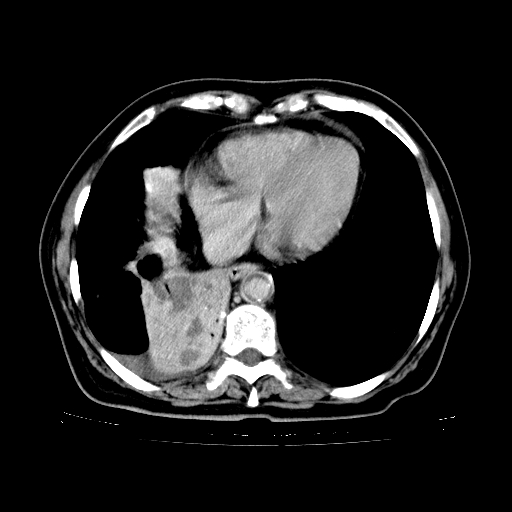

标题: CT23067:女,70岁,咳嗽、咳痰一个月,低热一周。 [打印本页]

女,70岁,咳嗽、咳痰一个月,低热一周。

2.胸主动脉夹层。

4、主动脉夹层。

5、右侧少量胸腔积液。

支持,首先一元论解释。胸主动脉部分层面环形低密度,中心强化。环形影不强化。不象真假腔的改变。我考虑动脉炎,不太支持夹层动脉瘤-和大家的观点不一致,希望楼主让患者再做个心血管的彩超吧。

继发型肺结核,右下肺支气管内膜结核.右侧少量胸腔积液.主动脉夹层.